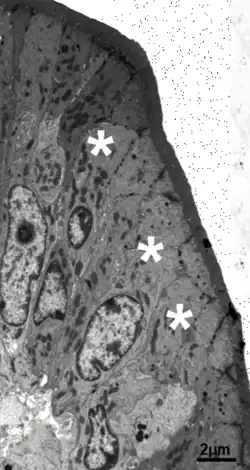

Microscopia Electrónica La ultraestructura del enterocito muestra orgánulos densamente empacados: numerosas mitocondrias, un retículo endoplasmático extenso, un aparato de Golgi grande y abundantes vacuolas y vesículas.

El borde en cepillo del polo apical está formado por microvellosidades, que son claramente visibles solo con grandes aumentos. Las microvellosidades son especializaciones de la membrana apical del enterocito.[2]

Con el microscopio electrónico las microvellosidades se observan como cilindros paralelos de 1 a 2 micrómetros (µm) de altura y 0,1µm de ancho;[1]

Por su eje central pasa un haz de filamentos que forman su esqueleto.

El citoplasma apical contiene numerosas cisternas del retículo endoplásmico liso (REL), el cual es necesario para la síntesis de triglicéridos. El retículo endoplásmico rugoso (RER) es extenso y se sitúa a mayor profundidad dentro de la célula. El complejo de Golgi es grande, muestra una posición supranuclear en estrecha relación con el RER. Las vesículas de pinocitosis y las vacuolas son muy abundantes debajo de la membrana apical y de la membrana basolateral.